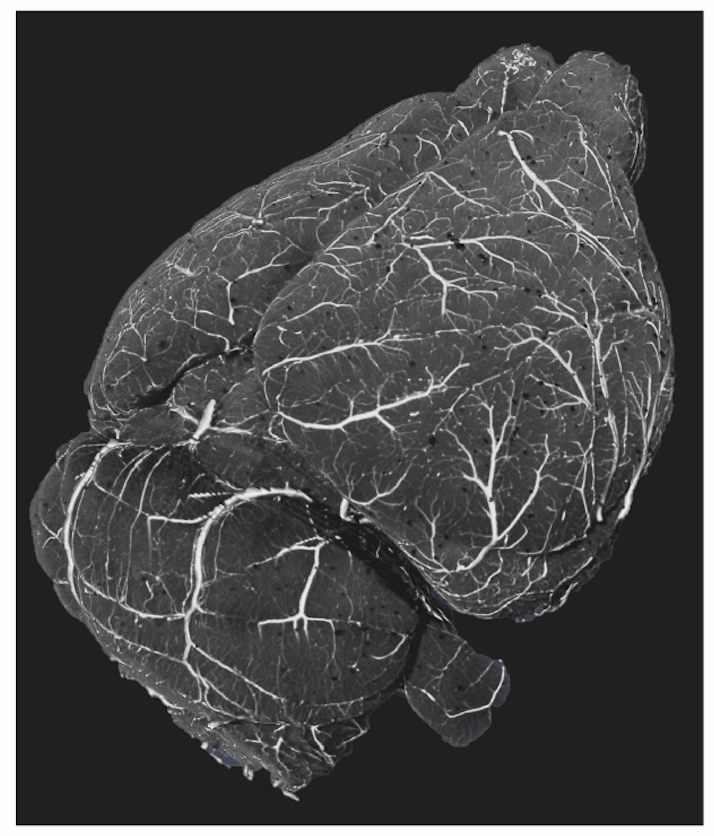

Our cerebrovascular paper is in BioRxiv. biorxiv.org/content/10.110… Here, we mapped total cerebrovasculature, pericyte, and glutamatergic and GABAergic neurons in the mouse brain. We found striking correlation with vasculature, PV, and nNOS neurons.